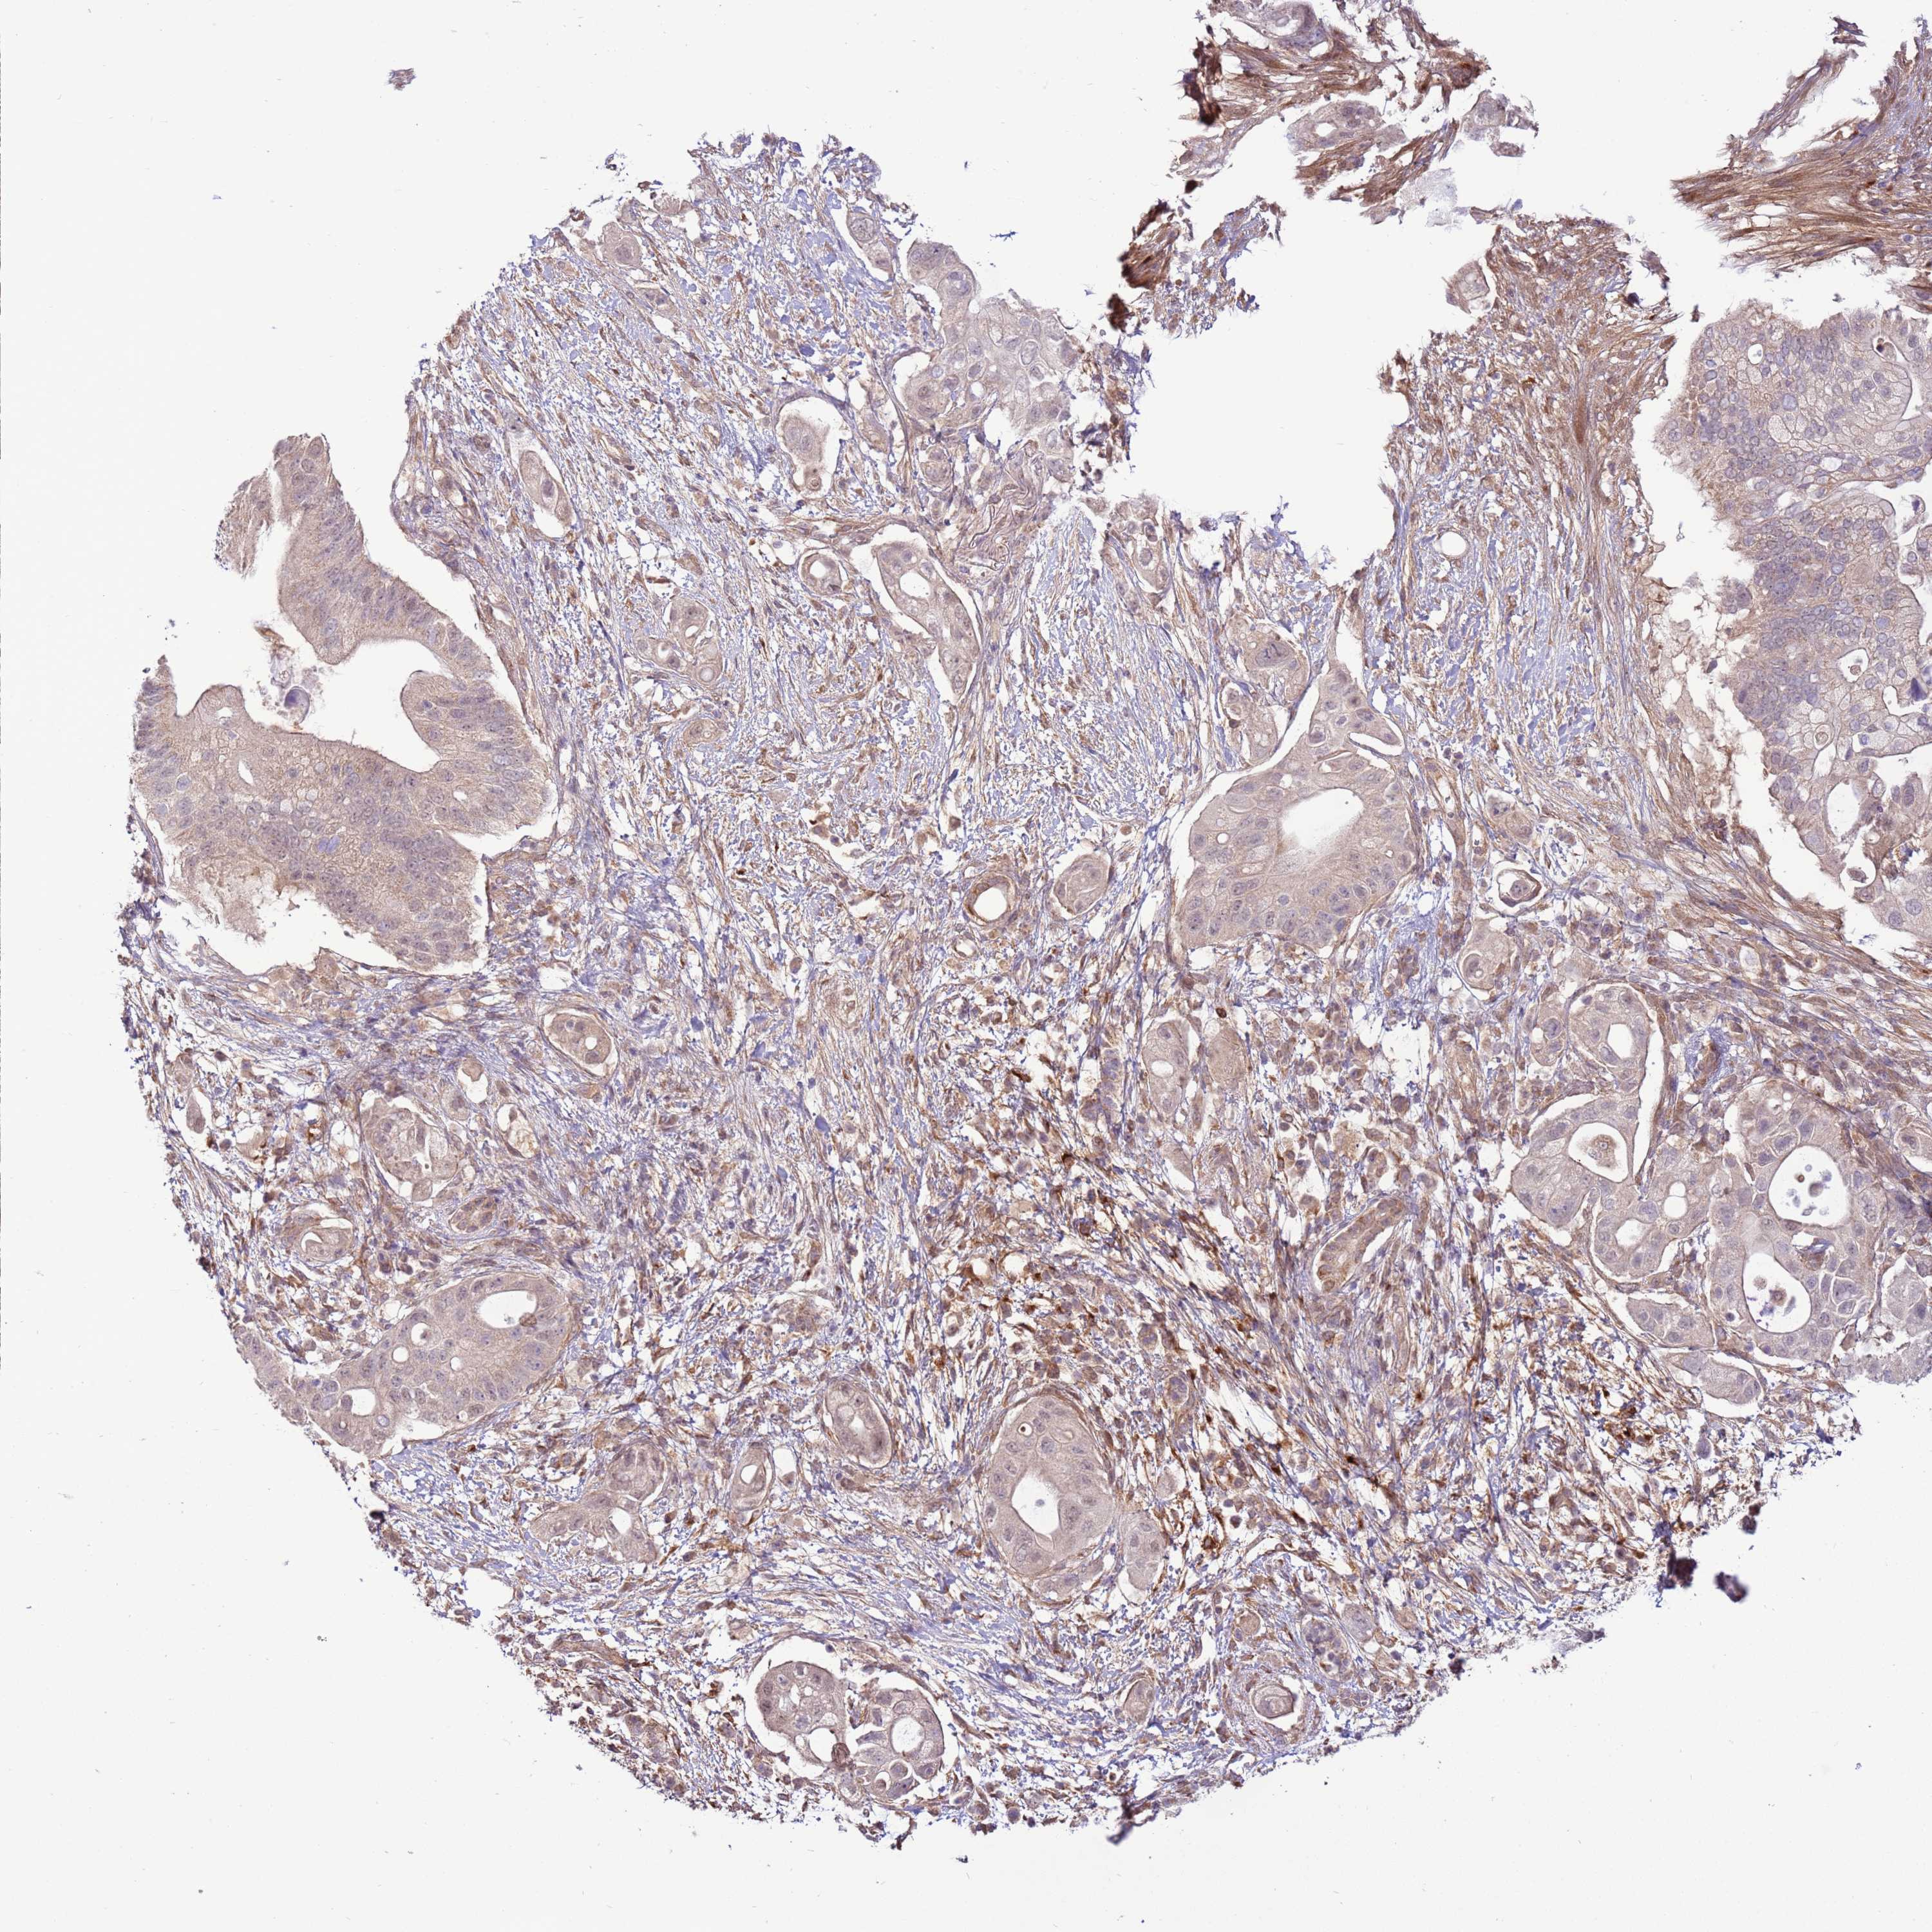

PANCREATIC CANCER - Protein expressioni

A mouse-over function shows sample information and annotation data. Click on an image to view it in a full screen mode. Samples can be filtered based on level of antibody staining by selecting one or several of the following categories: high, medium, low and not detected. The assay and annotation is described here.

Note that samples used for immunohistochemistry by the Human Protein Atlas do not correspond to samples in the TCGA dataset.

Antibody stainingi

Antibody staining in the annotated cell types in the current human tissue is reported as not detected, low, medium, or high, based on conventional immunohistochemistry profiling in selected tissues. This score is based on the combination of the staining intensity and fraction of stained cells.

Each image is clickable and will lead to virtual microscopy that enables deeper exploration of all samples and also displays staining intensity scores, fraction scores and subcellular localization as well as patient and tissue information for each sample.

Antibody HPA047386

Staining

High

Medium

Low

Not detected

Intensity

Strong

Moderate

Weak

Negative

Quantity

>75%

75%-25%

<25%

None

Location

Nuclear

Cytoplasmic/membranous

Cytoplasmic/membranous,nuclear

Adenocarcinoma, NOS